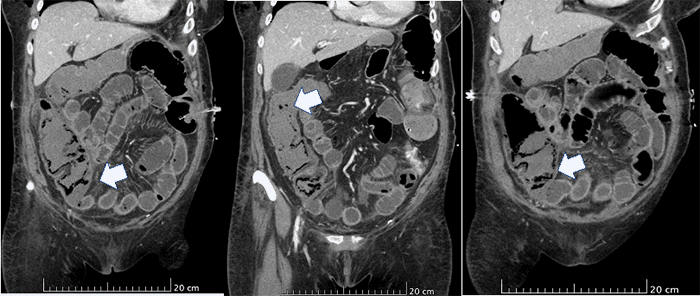

On postoperative day 5, the patient complained of acute abdominal pain that was disproportionate to her physical exam findings despite pain control with intravenous (IV) narcotics. Initially, anastomotic leak was suspected.1‒4 However, a CT scan of the abdomen and pelvis revealed a distended bowel and pneumatosis of the bowel wall and concerning tapering of the distal SMA (Figure 3). Given these findings, the patient was taken to the operating room for emergent exploration.

Figure 3. Abdominopelvic CT Scan Demonstrating Dilated Loops of Small and Large Bowel, with Distal Ileal and Right Colonic Ischemia Accompanied by Pneumatosis Intestinalis (arrow). Published with Permission